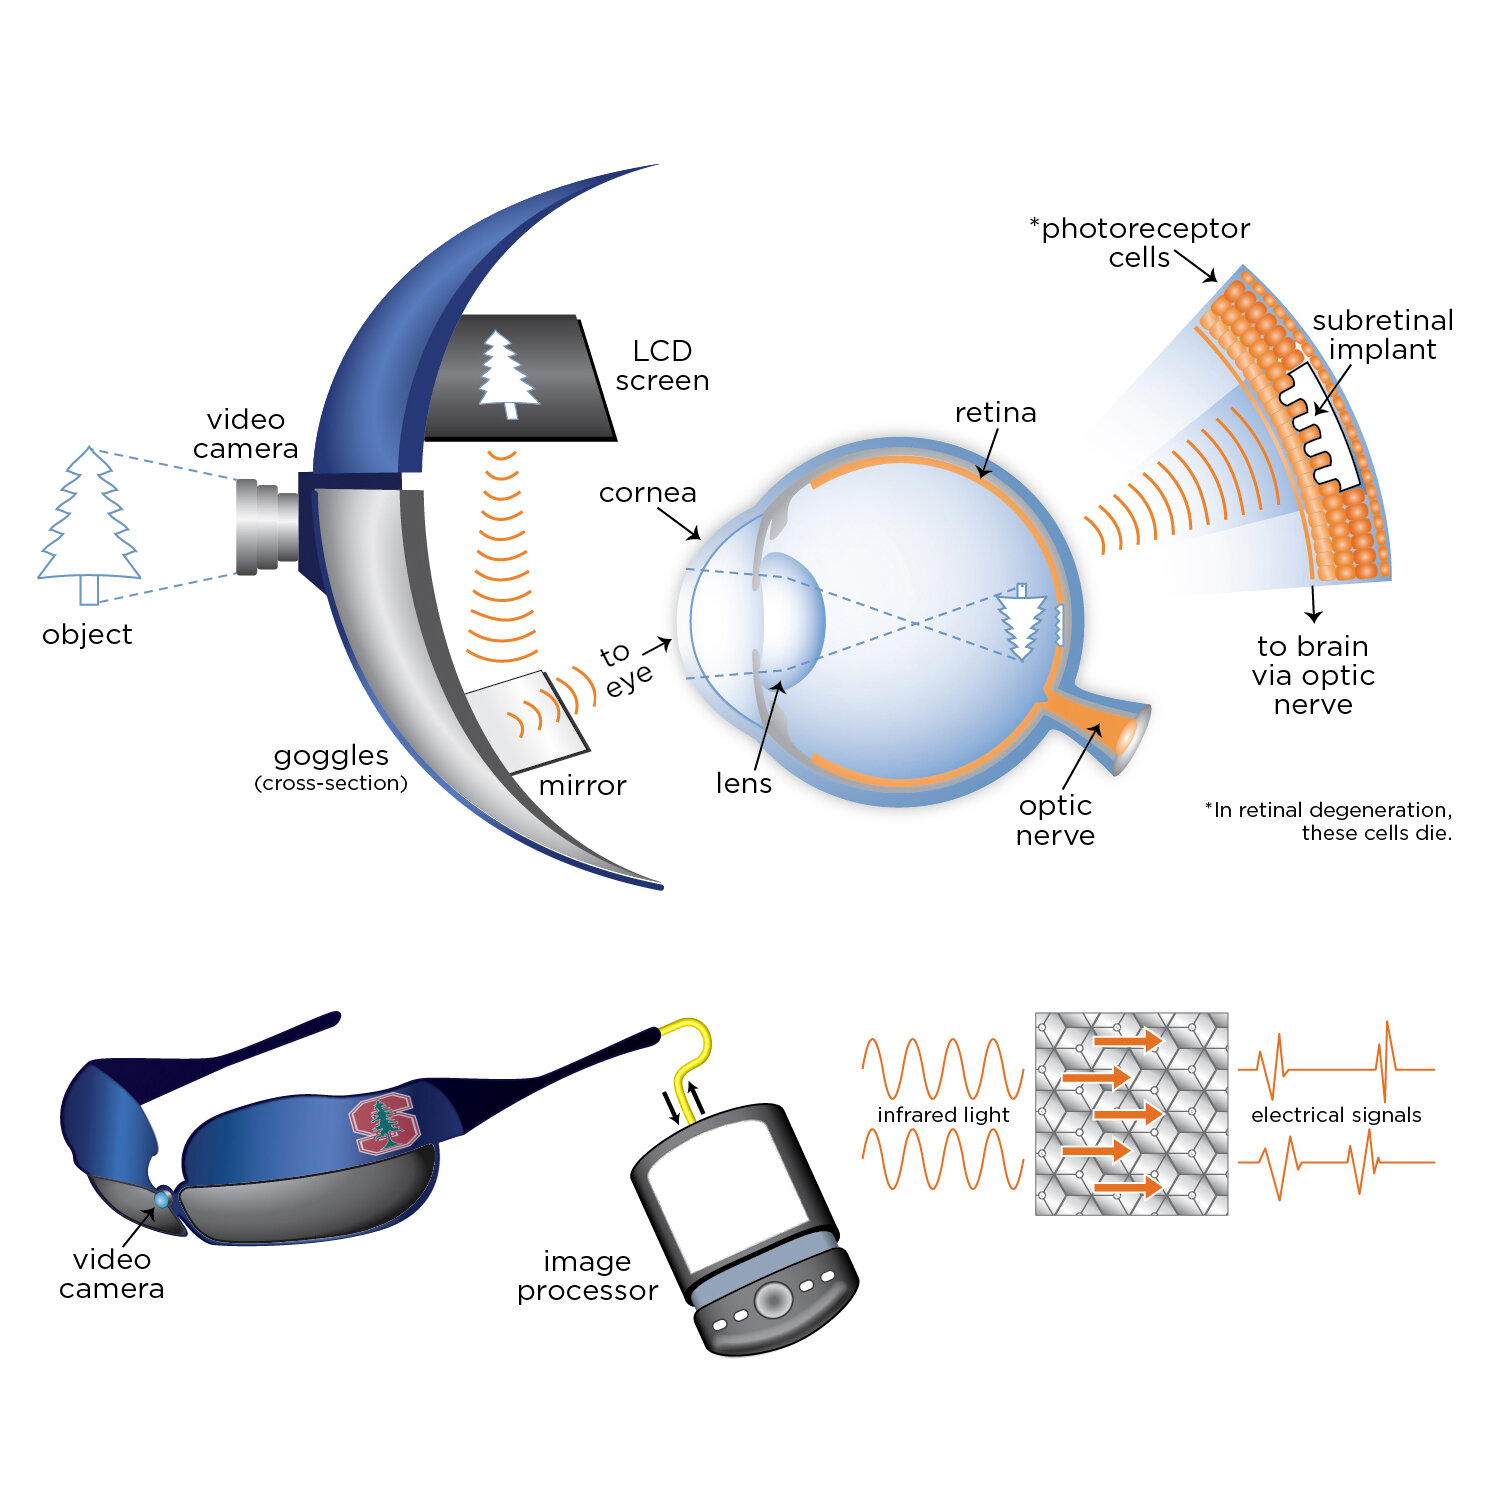

![Retinal goggles and implant to restore sight]()

Retinal goggles and implant to restore sight